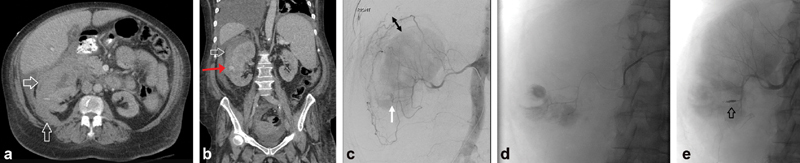

Case 2: Grade IV Renal Artery Injury after Percutaneous Nephrostomy

A 74-year-old man with nephrolithiasis and chronic kidney disease (Cr 1.5) presented to an outside hospital with bilateral obstructive nephrolithiasis. He underwent right percutaneous nephrostomy tube placement complicated by renal subcapsular hematoma leading to hemorrhagic shock requiring vasopressors and blood transfusions. Fig. 3 (a, b) demonstrates the retroperitoneal hematoma (white arrows) and percutaneous nephrostomy tube (red arrow). He was then transferred to the authors' institution for IR consultation. Right renal angiography ( Fig. 3c – e ) revealed active extravasation of contrast from two right renal artery inferior pole branch vessels. A microcatheter was used to select each bleeding area and microcoils used to embolize ( Fig. 3c–e : arrows—percutaneous nephrostomy tube and ureteral stent; arrowheads—postembolization coil pack).

Fig. 3.

Subcapsular hematoma after nephrostomy. Axial ( a ) and coronal ( b ) CT images showing large subcapsular hematoma after placement of a right percutaneous nephrostomy catheter (PCN). The PCN is partially imaged (red arrow). Angiogram shows two areas of active extravasation ( c ). Oblique angiogram shows microcatheter placing coils in the more central focus ( d ) and AP angiogram shows placement of more distal micro-coils ( e ) to treat the more peripheral focus of hemorrhage.